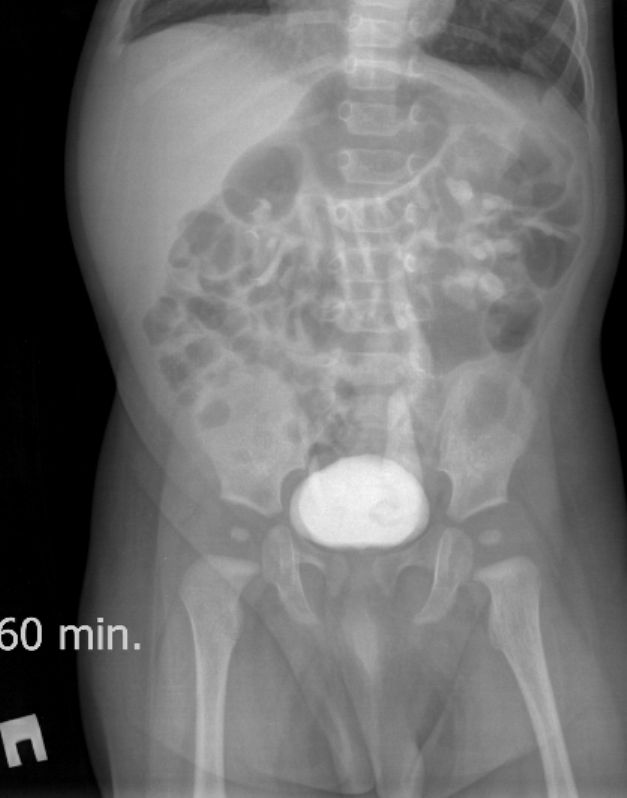

Экскреторные урограммы данного пациента :

На всех снимках определяется левосторонний уретерогидронефроз 3-й степени и левостороннее уретероцеле непостоянного размера. Справа - расширения собирательной системы почки не выявлено. На снимке на 15 минуте после введения контраста определяется уретероцеле справа небольших размеров, на последующих снимках достоверного его контрастирования нет.